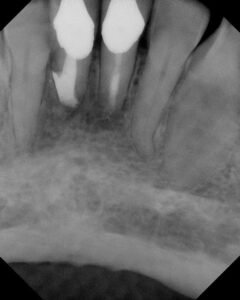

At one week, the patient reported some pain and throbbing following the treatment with increased mobility. We stabilized the teeth with some bonded resin and recommended Augmentin.

At two weeks, patient reported improvement, but gingival inflammation was present and #25 had a class III mobility. Teeth were removed from occlusion to remove any occlusal trauma. We recommended a second antibiotic at that time, Clindamycin.